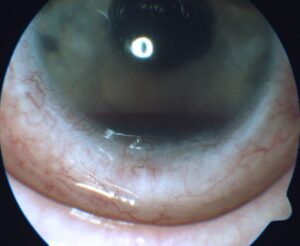

Slit lamp examination OD was remarkable for 2+ meibomian gland disease. Slit lamp examination OS was remarkable for 2+ meibomian gland disease, trace diffuse bulbar conjunctival injection, and trace bulbar conjunctival edema. The cornea had 3+ diffuse edema with guttata and 3 clock hours of pannus and neovascularization (Figure 1). The anterior chamber had a 1-mm tall hyphema (Figure 2) and anterior chamber reaction of 4+ cells and 1-2 flare. Clear and complete visualization of the iris was challenging due to the hyphema obstructing the inferior iris, 3+ corneal edema and 4+ cells and 1-2 flare anterior chamber reaction, making it difficult to completely rule out iris neovascularization. Posterior structures were also difficult to assess due to the corneal edema, hyphema and anterior chamber reaction. Therefore, a B-scan ultrasound was performed. No masses or retinal detachments were detected (Figure 3). Fundus examination and gonioscopy were performed only OD due to the presence of the hyphema OS. No abnormal vessels in the angles, angle neovascularization or other abnormalities were noted OD.

![]() Figure 1. Hyphema, 3+ corneal edema, pannus and corneal neovascularization of the left eye at initial visit. Click to enlarge |